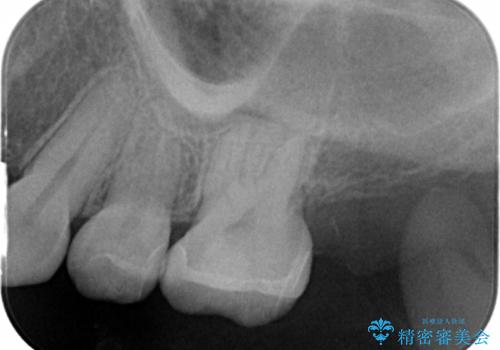

精査したところ、左上の奥歯の間(左上56間)にう蝕を認めました。

う蝕を丁寧に除去したのち、セラミックインレーによる修復を行いました。